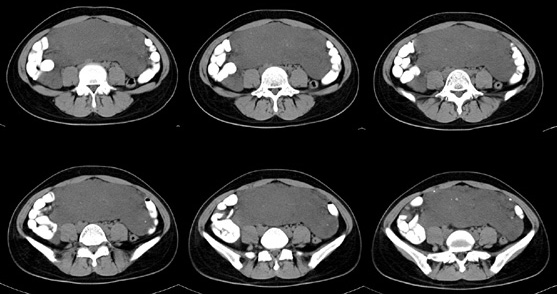

女性,28岁,停经3月,腹部膨隆1月,产前检查发现腹部占位

{肿块中心ct值27hu,增强后,动脉期、门脉期均无明显强化)

1 肠系膜肿块诸期无明显强化,肠系膜血管包绕其中但其周围仍见脂肪称“脂肪环征”;2 肠系膜血管远端较近端细,于重组像上见血管周围有强化结节为炎性结节,3肿块内见部分脂肪密度及少许点状钙化。4 腹膜后无肿大ln。

需与恶性病变鉴别,脂肪环征为重要点。亦需与卵巢源性肿瘤鉴别,年龄以及未见“卵巢静脉征”为要点。

患者手术病理:腹腔囊性淋巴管瘤,象这样充满整个腹腔的的确很少见